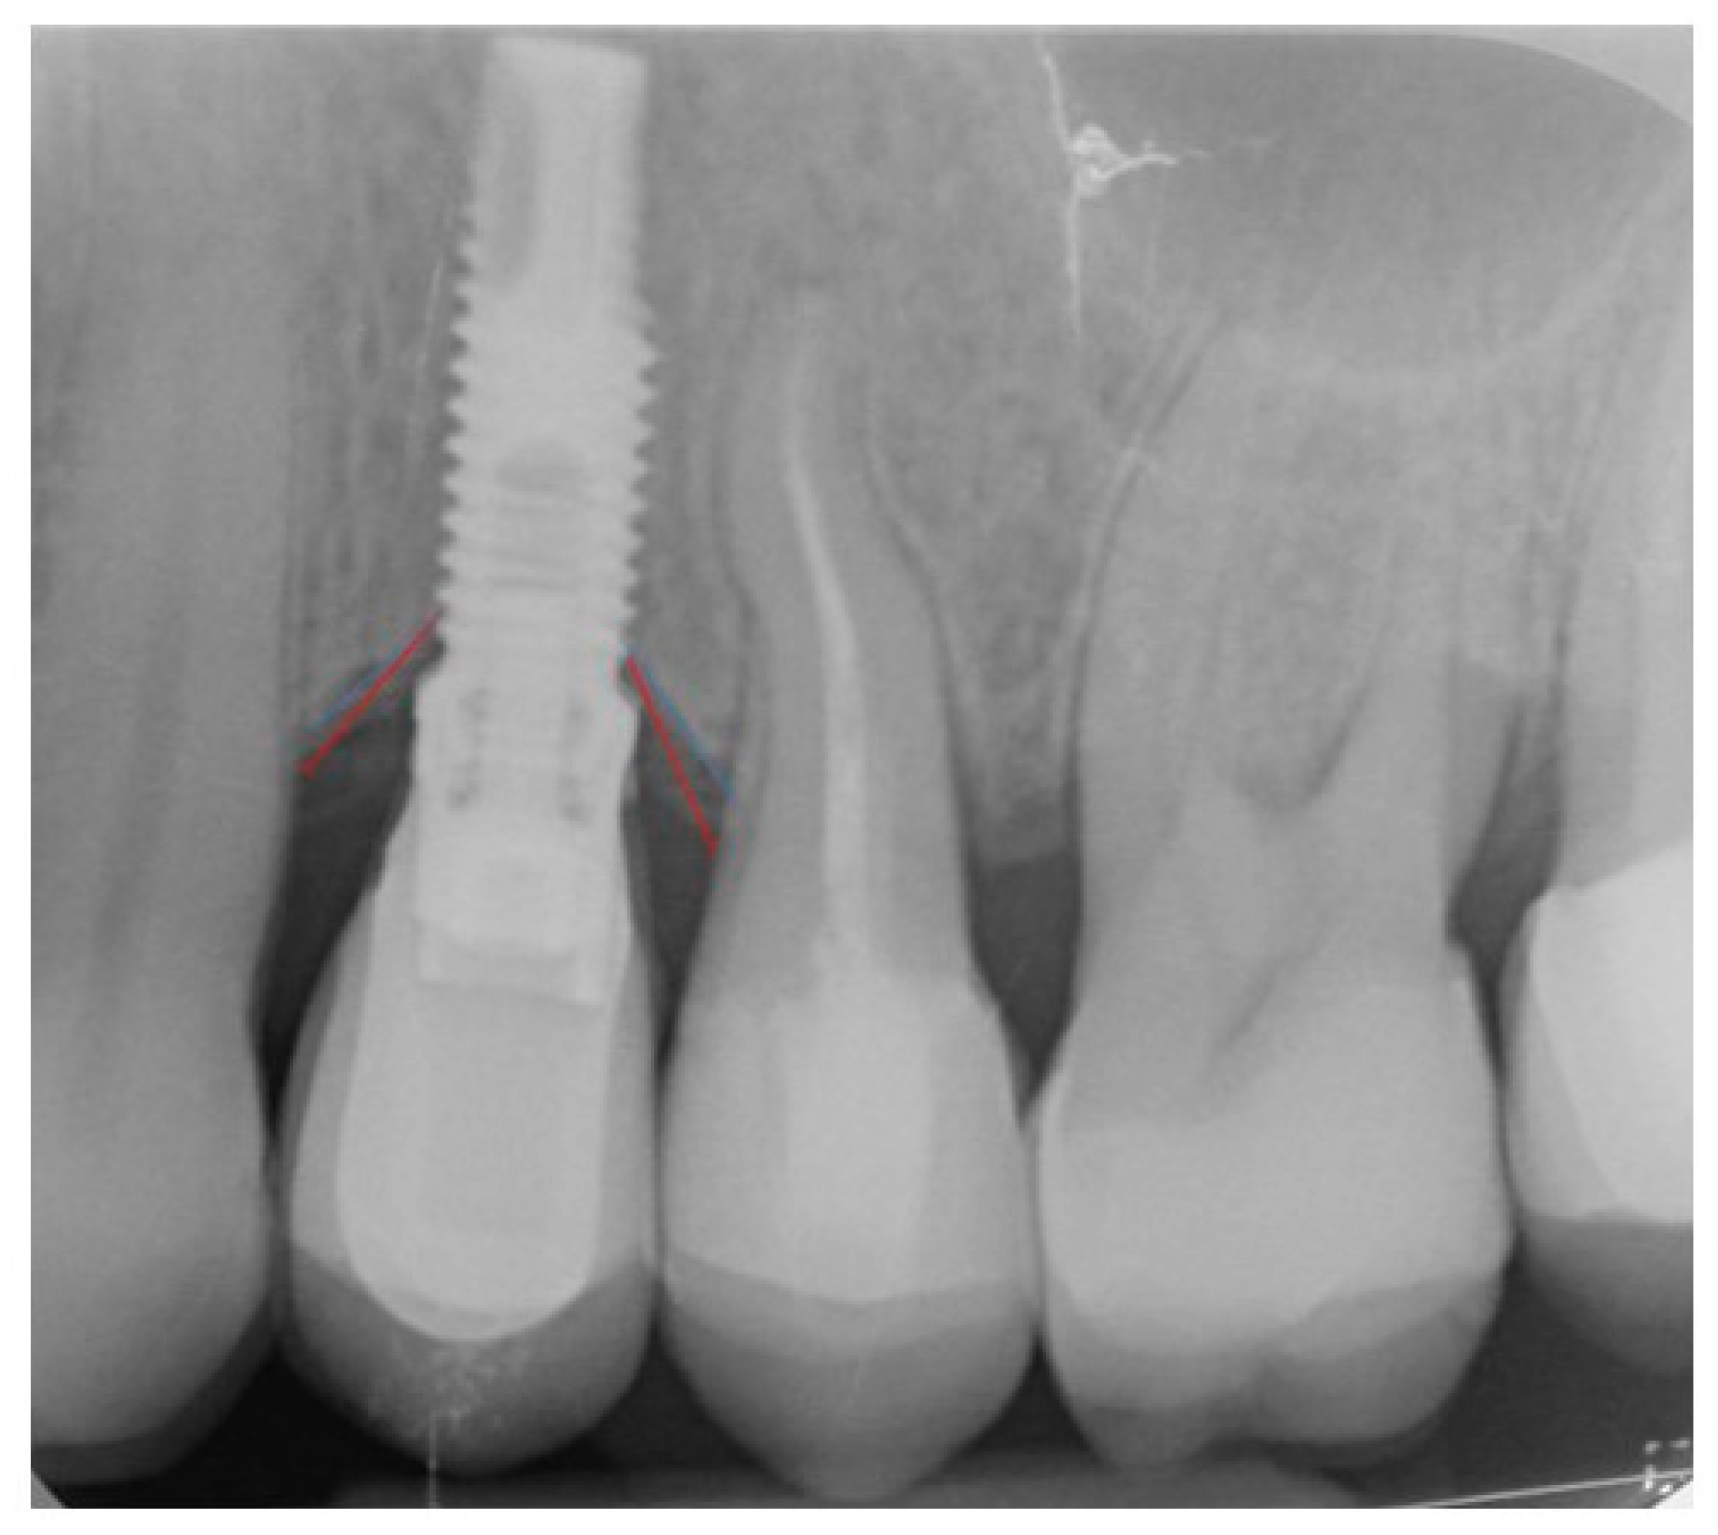

2. Materials and Methods

3. Results

| Angled Screw Channel Crowns | 3.7 (±0.48) | 4 (±0.66) | 0/10 | 2/10 | −0.25 (±0.15) |

| Cemented Crowns | 3.3 (±0.48) | 3.7 (±0.82) | 2/10 | 2/10 | −0.29 (±0.11) |

| p = (* < 0.05) | 0.08 | 0.383 | 0.446 § | 0.32 | |